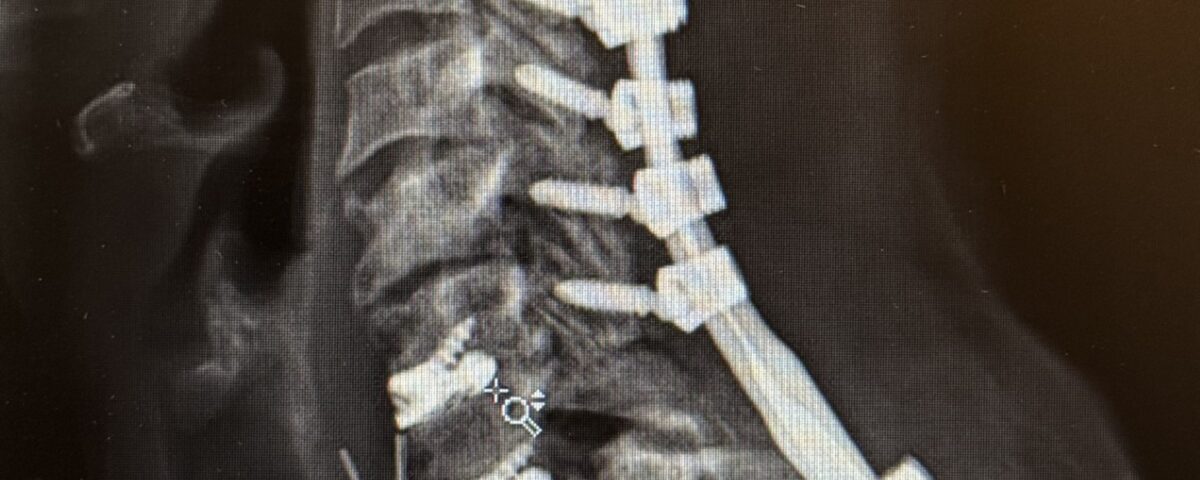

Her rheumatologist ordered an x-ray which showed anterolisthesis of C7-T-1 with kyphosis and instability (Fig 1 right).